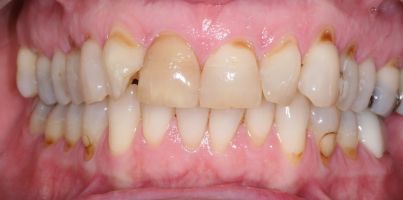

Before

After